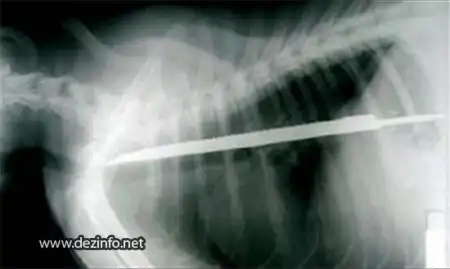

Детскую стрелу длиной в 25см проглатила собачка Бетти. Длинна самой Бетти всего 30 см.